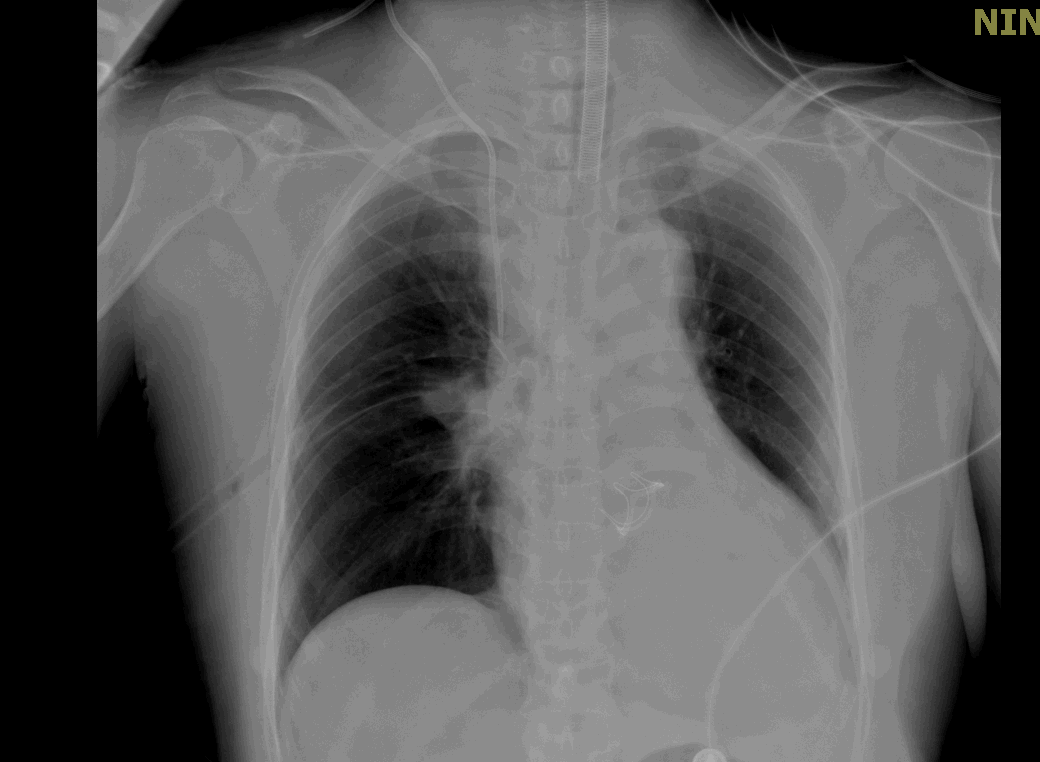

术后当天胸部X线正位片

为什么叫哈巴狗钳2023学术荟萃|王云:右侧肋间小切口体外循环心脏手术_https://www.jmylbn.com_新闻资讯_第15张